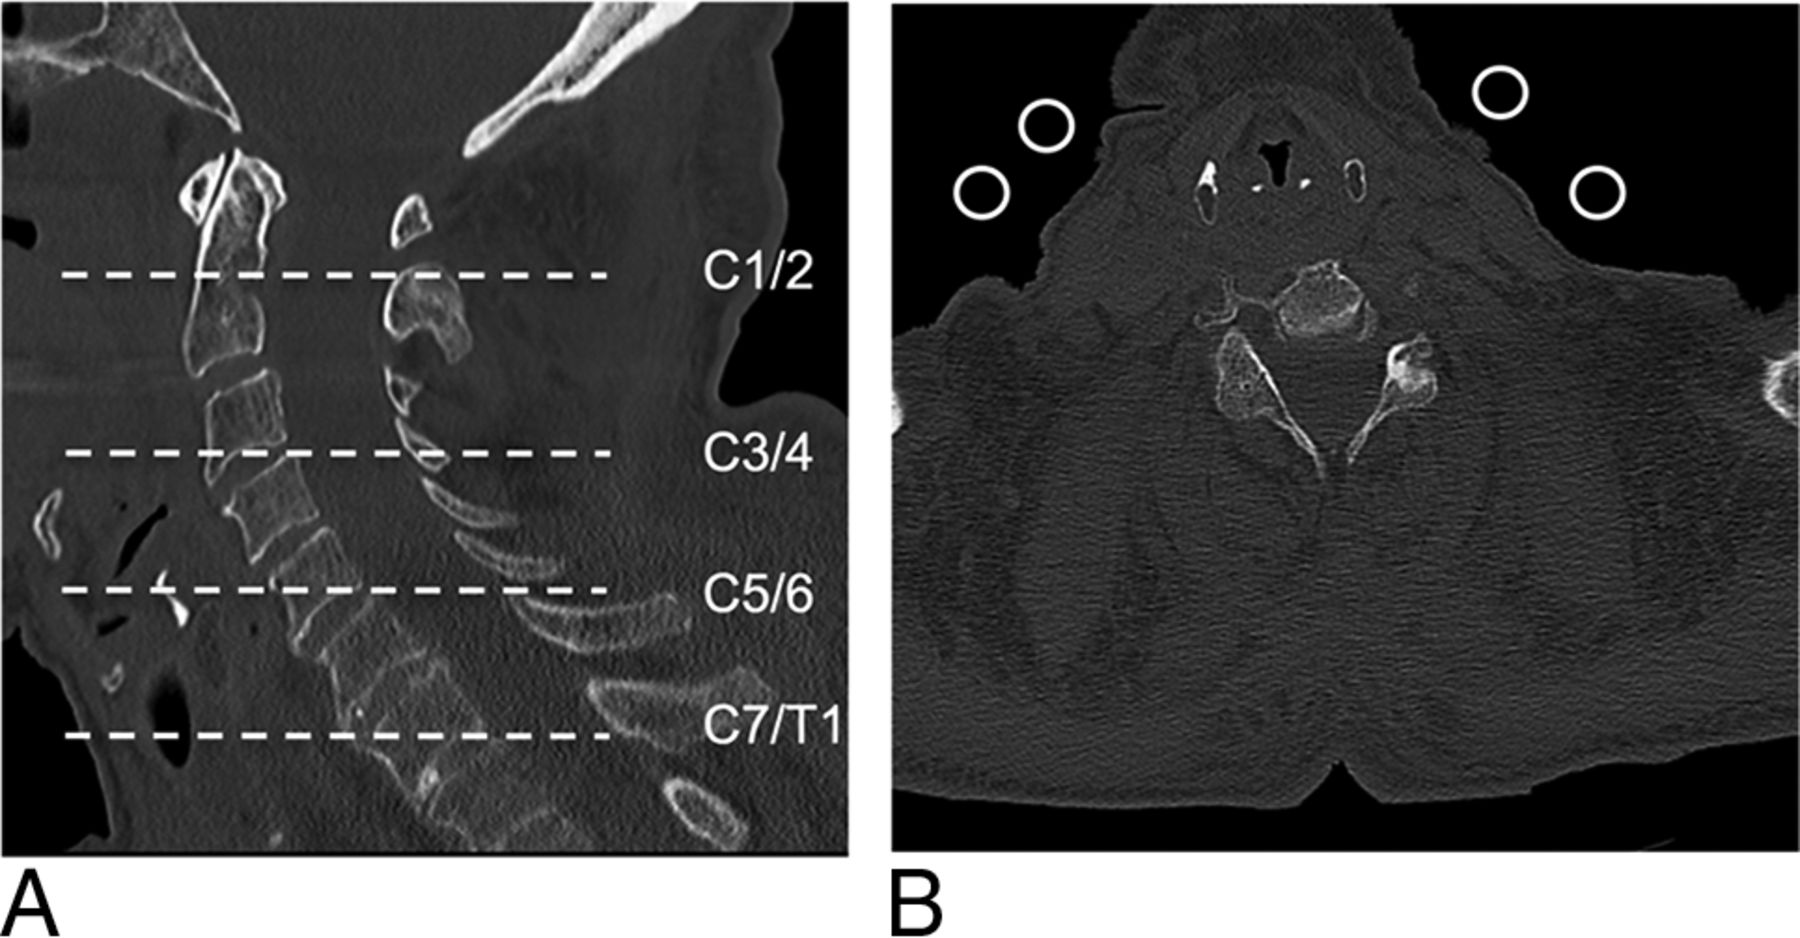

Four circular ROIs of 100 mm2 each at the cervical spine levels (C1–2, C3–4, C5–6, and C7–T1) served for noise measurements. They were placed in the extracorporeal air on axial images at exactly the same level in each scan of the same cadaver by 1 reader with 2 years of experience in spine imaging (Fig 2). Image noise was defined as the SD of the mean CT numbers measured in Hounsfield units within an ROI.

Quantitative and qualitative image noise were evaluated on 4 different cervical spine levels (A, dashed lines). Axial image (B) at level C5–6 shows 4 ROIs of 100 mm2 each in the extracorporeal air for quantitative noise measurements.